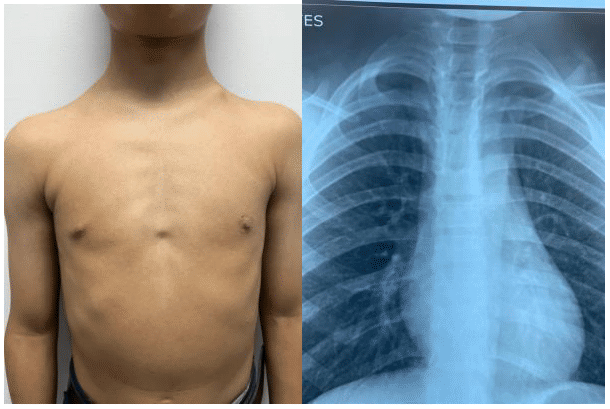

A 13-year-old male presented to the maxillofacial surgery department for retained dental organ extraction. Clinical examination revealed dolichocephaly, a rectangular face, underdeveloped facial skeleton, flattened frontal bone, acro-osteolysis, and a triangular torso. There was no reported family history of similar conditions.

Radiographic studies including posteroanterior (PA) and lateral skull radiographs, PA chest radiograph, PA and lateral spine radiograph, and maxillary tomography were obtained (Figure 1).

Figure 1 Frontal photograph depicting the triangular torso and posteroanterior (PA) chest radiograph showing a triangular shape of the thoracic cage and partial development of the clavicles.